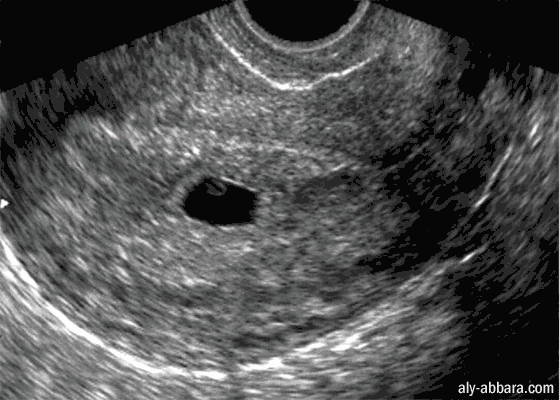

Utérus gravide contenant une grossesse débutante de 5 à 6 semaines d'aménorrhée

Echographiquement on distingue la grossesse sous forme de sac gestationnel de 14 mm de grand diamètre

avec sa couronne trophoblastique qui entoure le cœlome externe contenant la vésicule ombilicale ;

l'embryon n'est pas encore visible